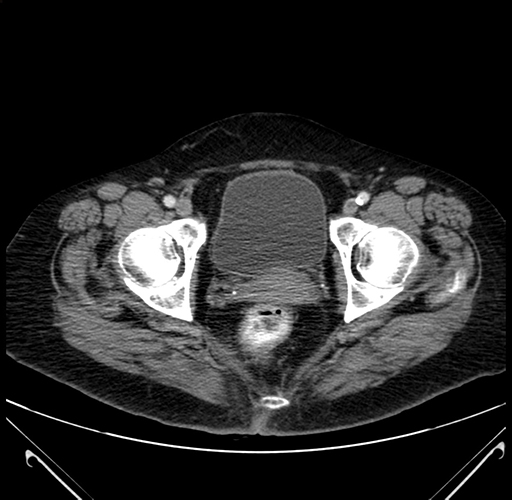

Axial Venous